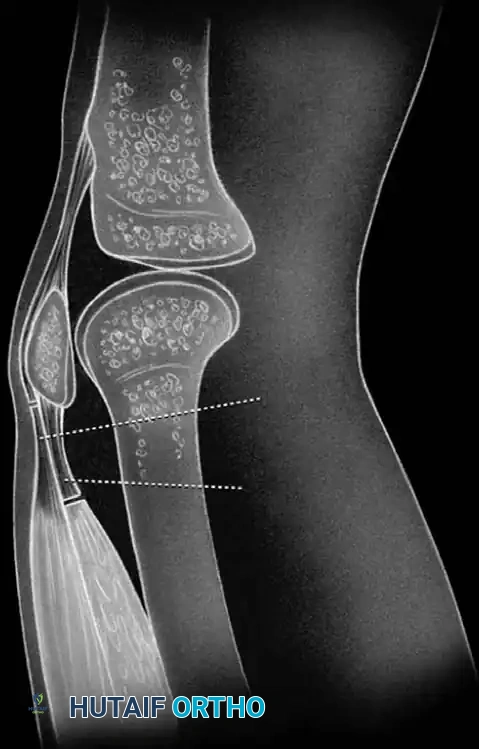

STAGE 4: Vastus Intermedius Transection

* If flexion remains inadequate, proceed to transect the previously mobilized vastus intermedius at a level near its musculotendinous junction. This eliminates the primary tethering force binding the extensor mechanism to the femoral shaft.